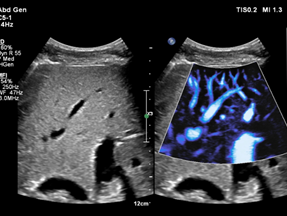

极速运算+人工智能AITT,飞利浦国产EPIQ 7C为心血管定量技术领域树立了更高更新的标准。获得FDA和NMPA双认证的AI技术,3D Auto MV三维自动二尖瓣定量,可自动建模追踪分析,快速获取二尖瓣三维模型,瓣叶及瓣环等多参数多时相运动功能曲线。AAA 腹主动脉瘤评估,快速获取腹主动脉容积数据,数字化综合评估腹主动脉瘤样病变进展。

图片

3D Auto MV三维自动二尖瓣定量

AAA  腹主动脉瘤评估